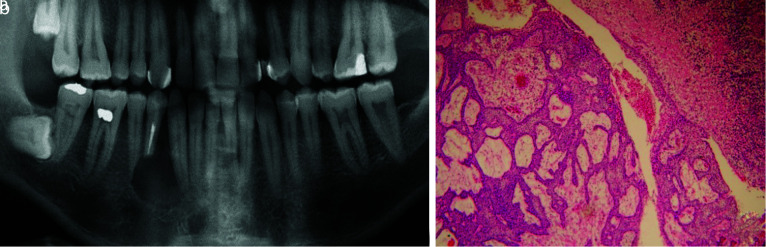

Results:  In the present study, 474 cases were diagnosed with a periapical cyst/granuloma clinico-radiographically, of which 61 cases (12.86%) received a microscopic diagnosis of a non-endodontic pathology. The most frequent lesion was odontogenic keratocyst (n= 12, 19.67%) followed by infected odontogenic cyst (n= 12, 19.67%). About 21.31% of diagnoses were non-cystic lesions and 4.9% were malignancies. The most odontogenic tumors that were diagnosed as periapical cyst/granuloma in clinico-radiography were the ameloblastoma variants (n= 4, 6.55%).

Conclusion:  A wide variety of microscopic diagnoses, including aggressive lesions such as ameloblastoma, as well as other malignant lesions was noted in this study. These misdiagnoses can lead to an inappropriate treatment plan. It is important to microscopically examine all lesions removed from the jaw.

Abstract Image